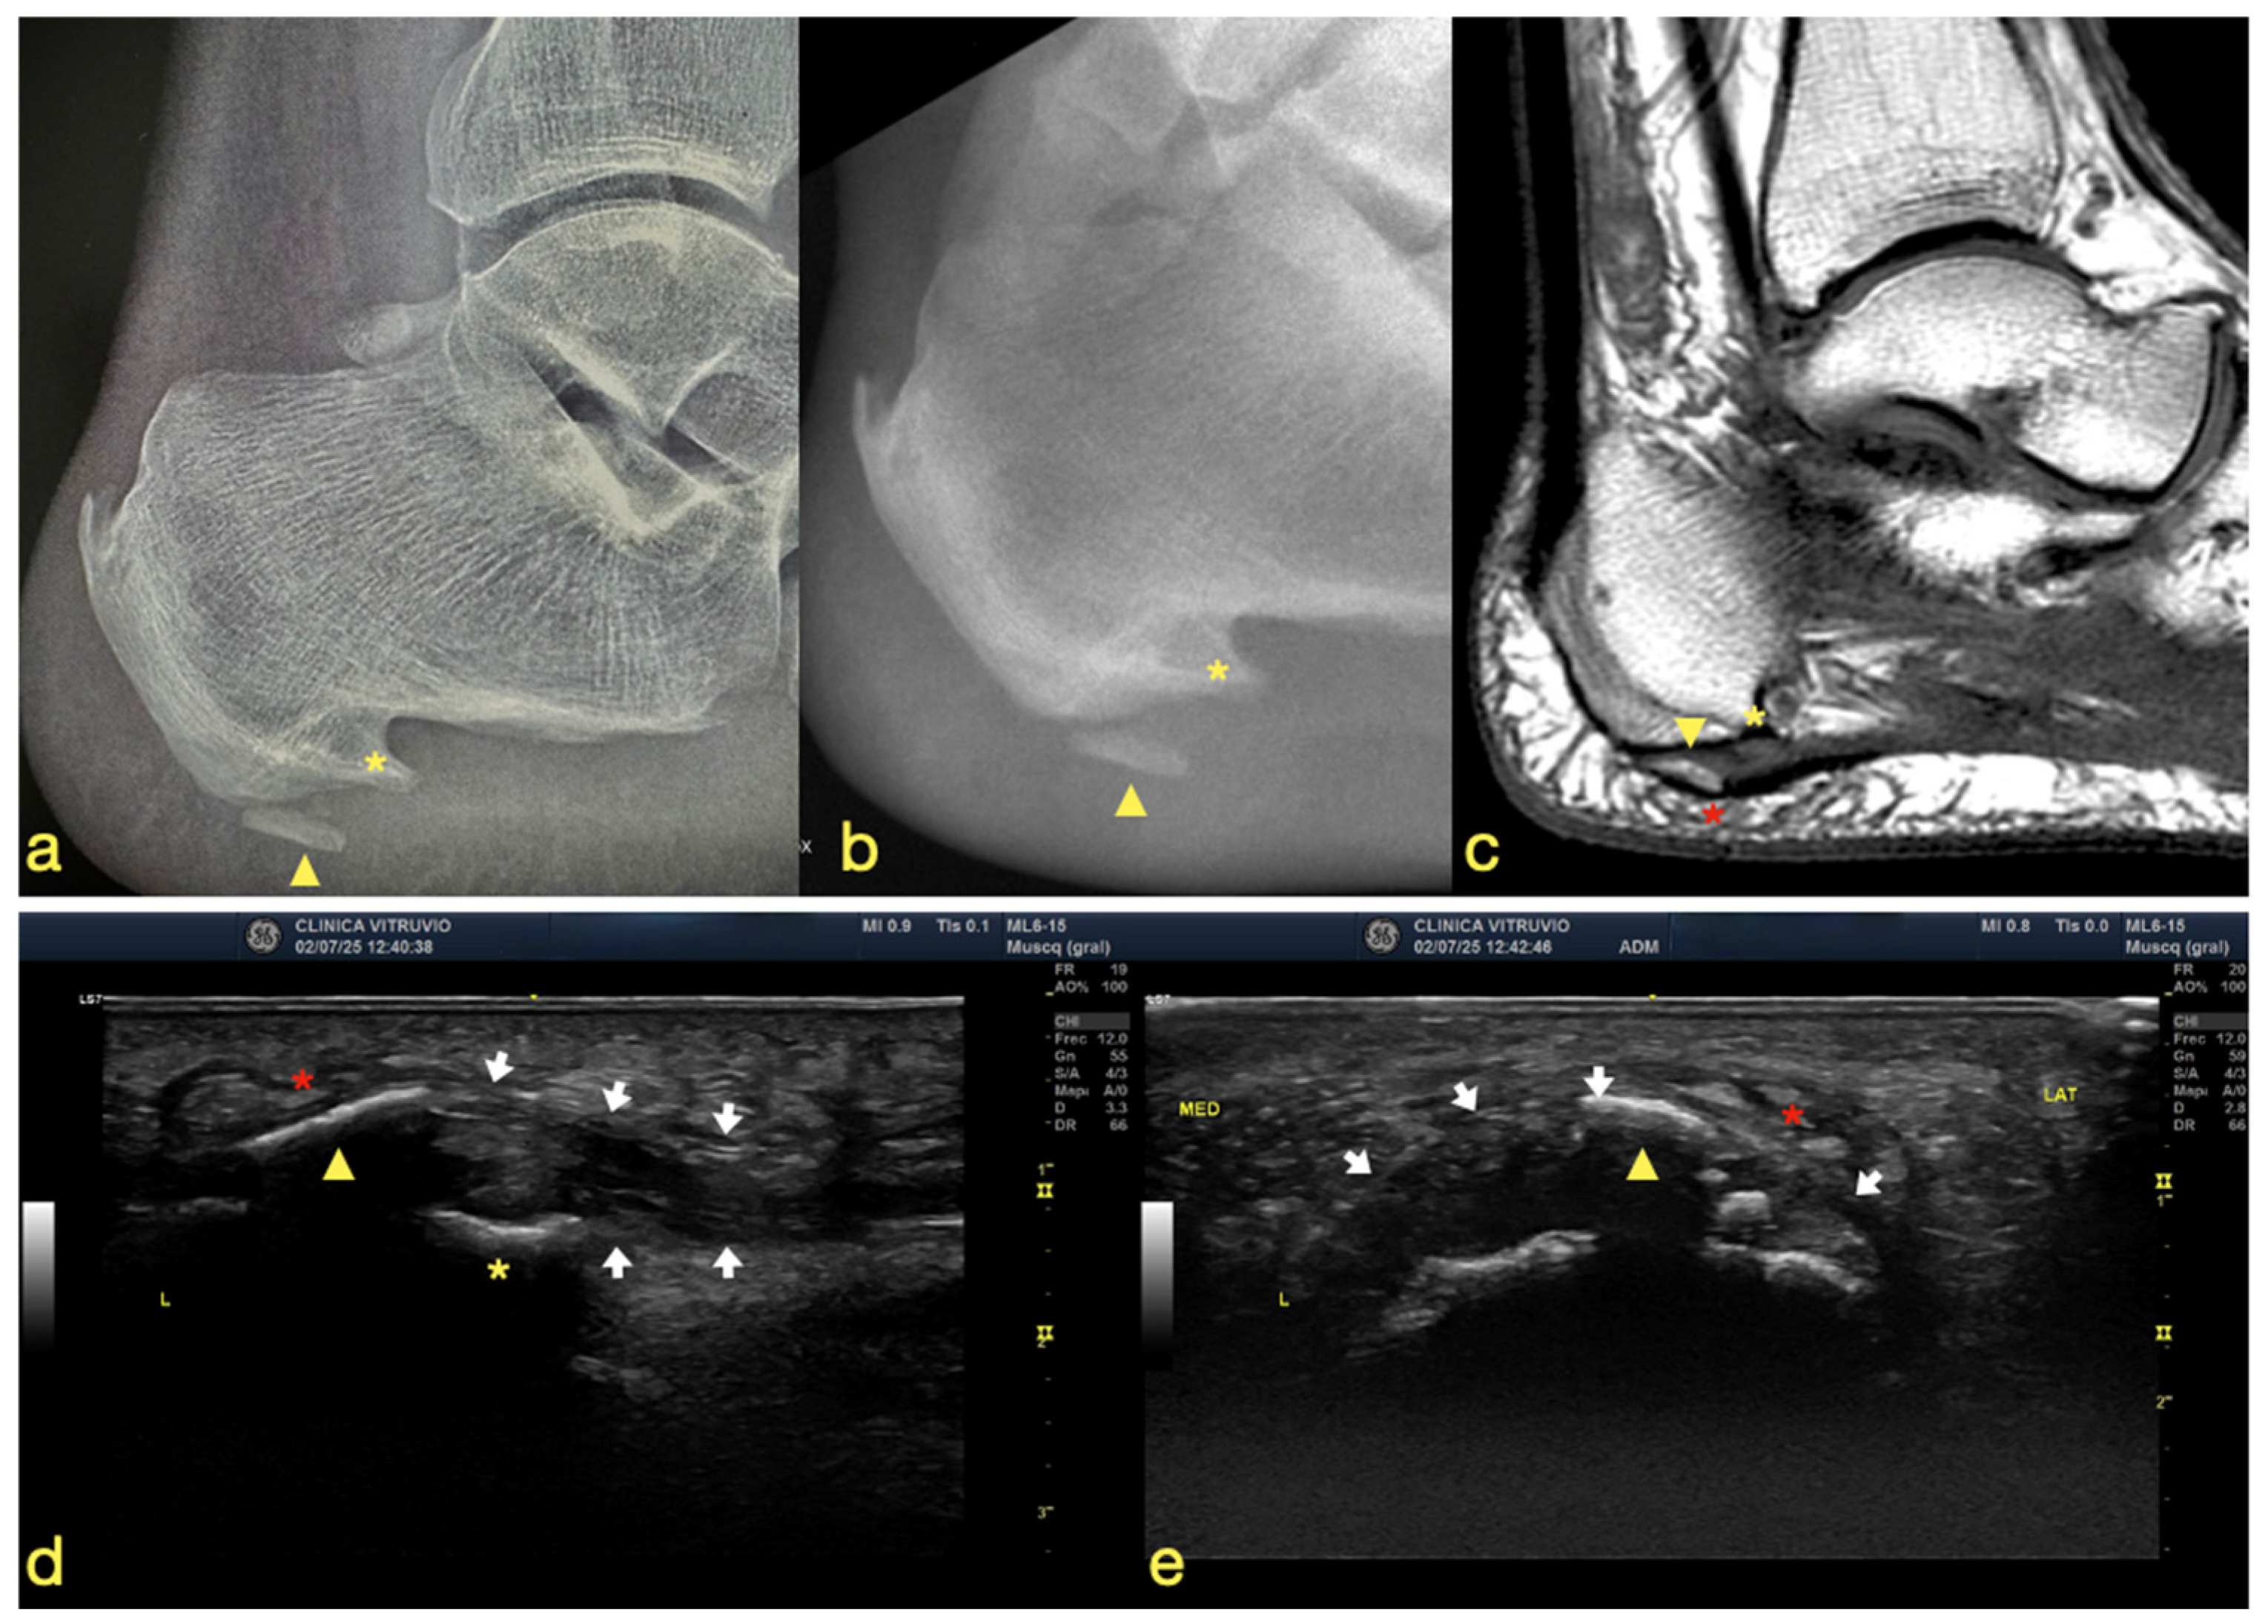

We report the case of an 82-year-old male patient. He has a medical history of high blood pressure and high uric acid levels, and he previously underwent a prostatectomy. The patient experienced plantar heel pain for two years, which became worse with weight-bearing activities. The pain was not linked with post-static dyskinesia and intensified when walking barefoot or on hard surfaces. He described the sensation as feeling like “walking on a stone.” For diagnostic purposes, plain radiographs and magnetic resonance imaging (MRI) were performed in order to establish a differential diagnosis and to confirm the presence of heterotopic ossification at the plantar fascia (Figure 1). The diagnosis of heterotopic ossification was established upon identifying a bone formation with visible trabeculae within the substance of the plantar fascia and a clear separation from the bony insertion, allowing differentiation from a calcaneal spur or enthesophyte.

Figure 1. (a) Plain radiograph, (b) fluoroscopic image, (c) MRI scan, (d) longitudinal (long-axis) ultrasound of the plantar fascia, and (e) transverse (short-axis) ultrasound of the plantar fascia. The yellow asterisk indicates the plantar enthesophyte (heel spur), the yellow arrowhead denotes the intrafascial heterotopic ossification, the white arrows outline the plantar fascia, and the red asterisk highlights the lesion involving the macrocameras of the plantar fat pad.